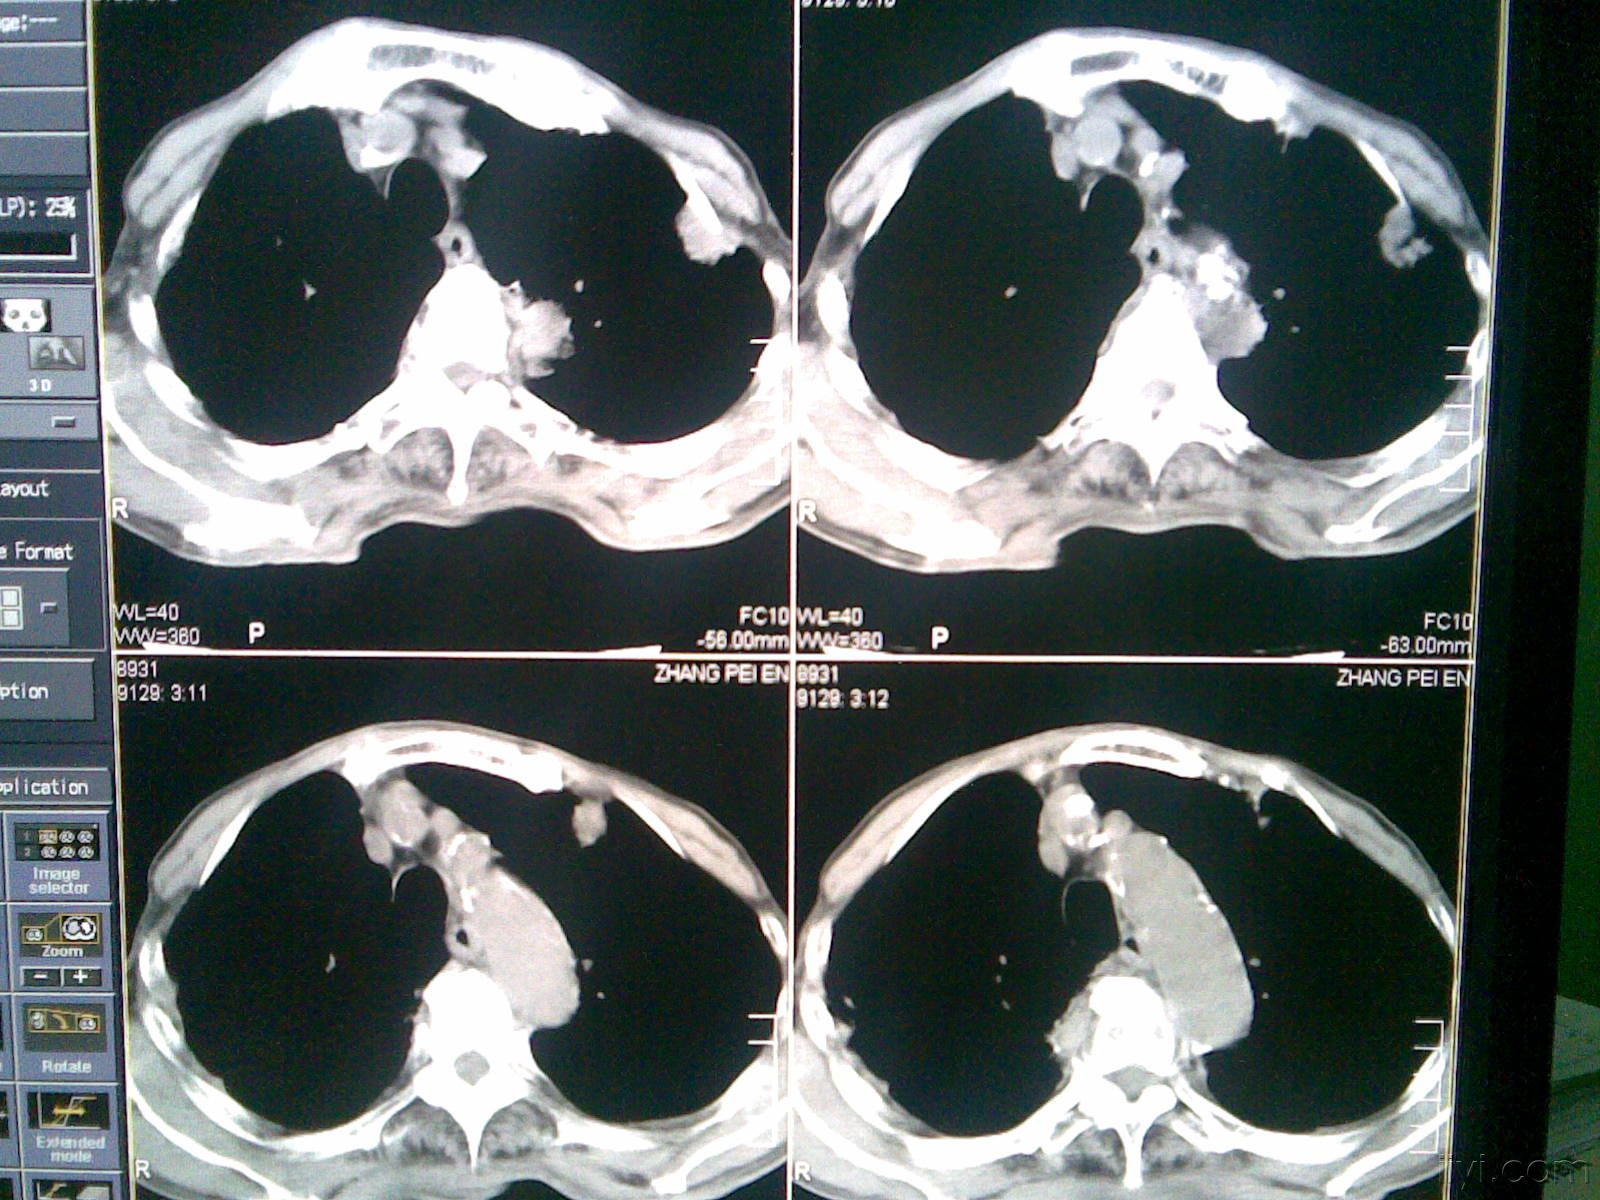

_右肺纖維化CT檢查

_右肺纖維化病灶

_特發性肺纖維化ct表現圖